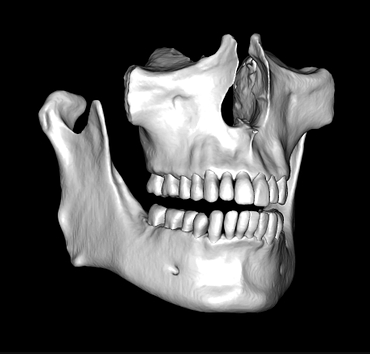

This is one feature that actually made Diagnocat very popular early on. It was the only software that made CBCT segmentation easy. Nowadays, there are several different companies and software that carry out segmentation. Diagnocat was the first and is still arguably the best at it.

So what is Segmentation? It basically means taking the CBCT and delineating all the different 3D structures, bones, individual teeth, etc.

These can then be individually exported via the software by generating STL files from CBCT dicom data. This can be used in other dental software. Jaw STLs can be used in Modjaw (jaw motion capture) for TMJ analysis, for example. As well as in exocad to help visualize the jaws for surgical planning or guide creation.

Being able to take a DICOM file and turn it into STLs is useful for a host of different CAD/CAM indications.

CBCT Segmentation into STL

Generate STL files from CBCT DICOM data.

Generate maxilla and mandible in one STL file or face, teeth, maxilla, mandible, airway, cranial base, canals as separate STL files.